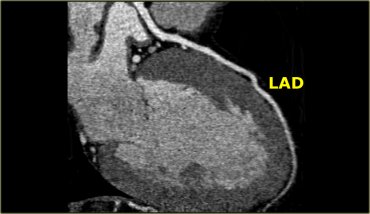

The LAD travels in the anterior interventricular groove and continues up to the apex of the heart.

The LAD supplies the anterior part of the septum with septal branches and the anterior wall of the left ventricle with diagonal branches.

The LAD supplies most of the left ventricle and also the AV-bundle.

The diagonal branches come off the LAD and run laterally to supply the antero-lateral wall of the left ventricle.

The first diagonal branch serves as the boundary between the proximal and mid portion of the LAD (2).

There can be one or more diagonal branches: D1, D2 , etc.